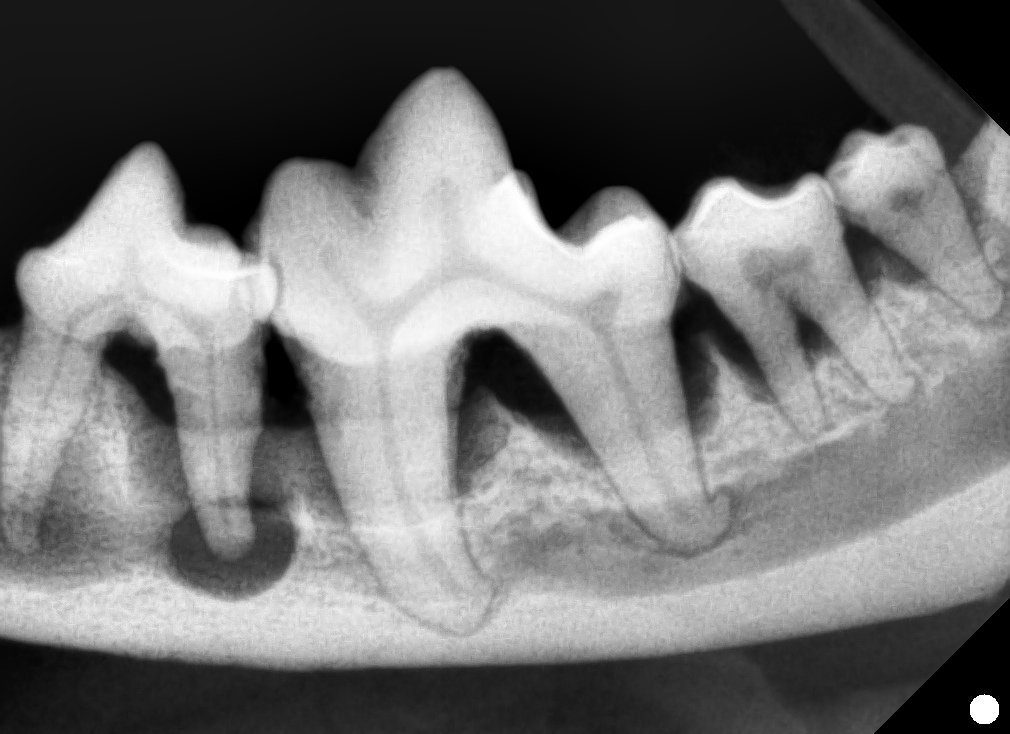

診断結果は「歯周トラブル」

ハナはその場で全身麻酔をかけられ、

奥歯を抜く大手術をすることに…